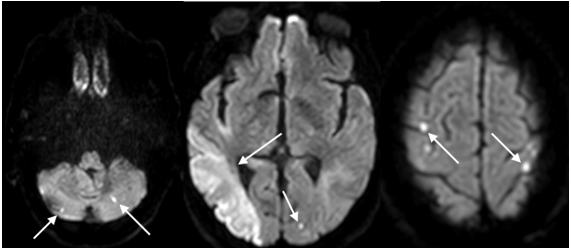

Durante a internação e investigação neoplásica, o paciente apresentou novo déficit neurológico agudo (alteração visual) 16 dias após o evento isquêmico inicial, sendo reavaliado, com confirmação de novo AVC isquêmico em região temporal direita e occipital direita, além de inúmeros novos focos isquêmicos embólicos (Figura 4).

Figura 4: Novo AVC isquêmico com sinal dos 3 territórios. Imagens de RNM – DWI mostrando múltiplas lesões de alta intensidade de sinal nos hemisférios cerebrais e cerebelares envolvendo três territórios vasculares diferentes.

No presente estudo relatamos o caso de um paciente com AVC cujo exame de imagem inicial apresentava isquemia em 3 territórios cerebrais sem alterações cardioembólicas que justificassem, havendo recorrência de novos eventos isquêmicos no decorrer da hospitalização. A análise desse contexto permite evidenciar que a investigação de câncer sistêmico deve ser considerada em pacientes cuja origem do AVC não é clara ou que apresentam recorrência vascular precoce. O AVC como primeira manifestação de uma neoplasia maligna subjacente é, em sua maioria, secundário a causas específicas relacionadas ao câncer. O desfecho é desfavorável e se correlaciona tanto com a gravidade da incapacidade neurológica quanto com o estágio do tumor (TACCONE et al., 2008; ABOELFARH et al., 2024).